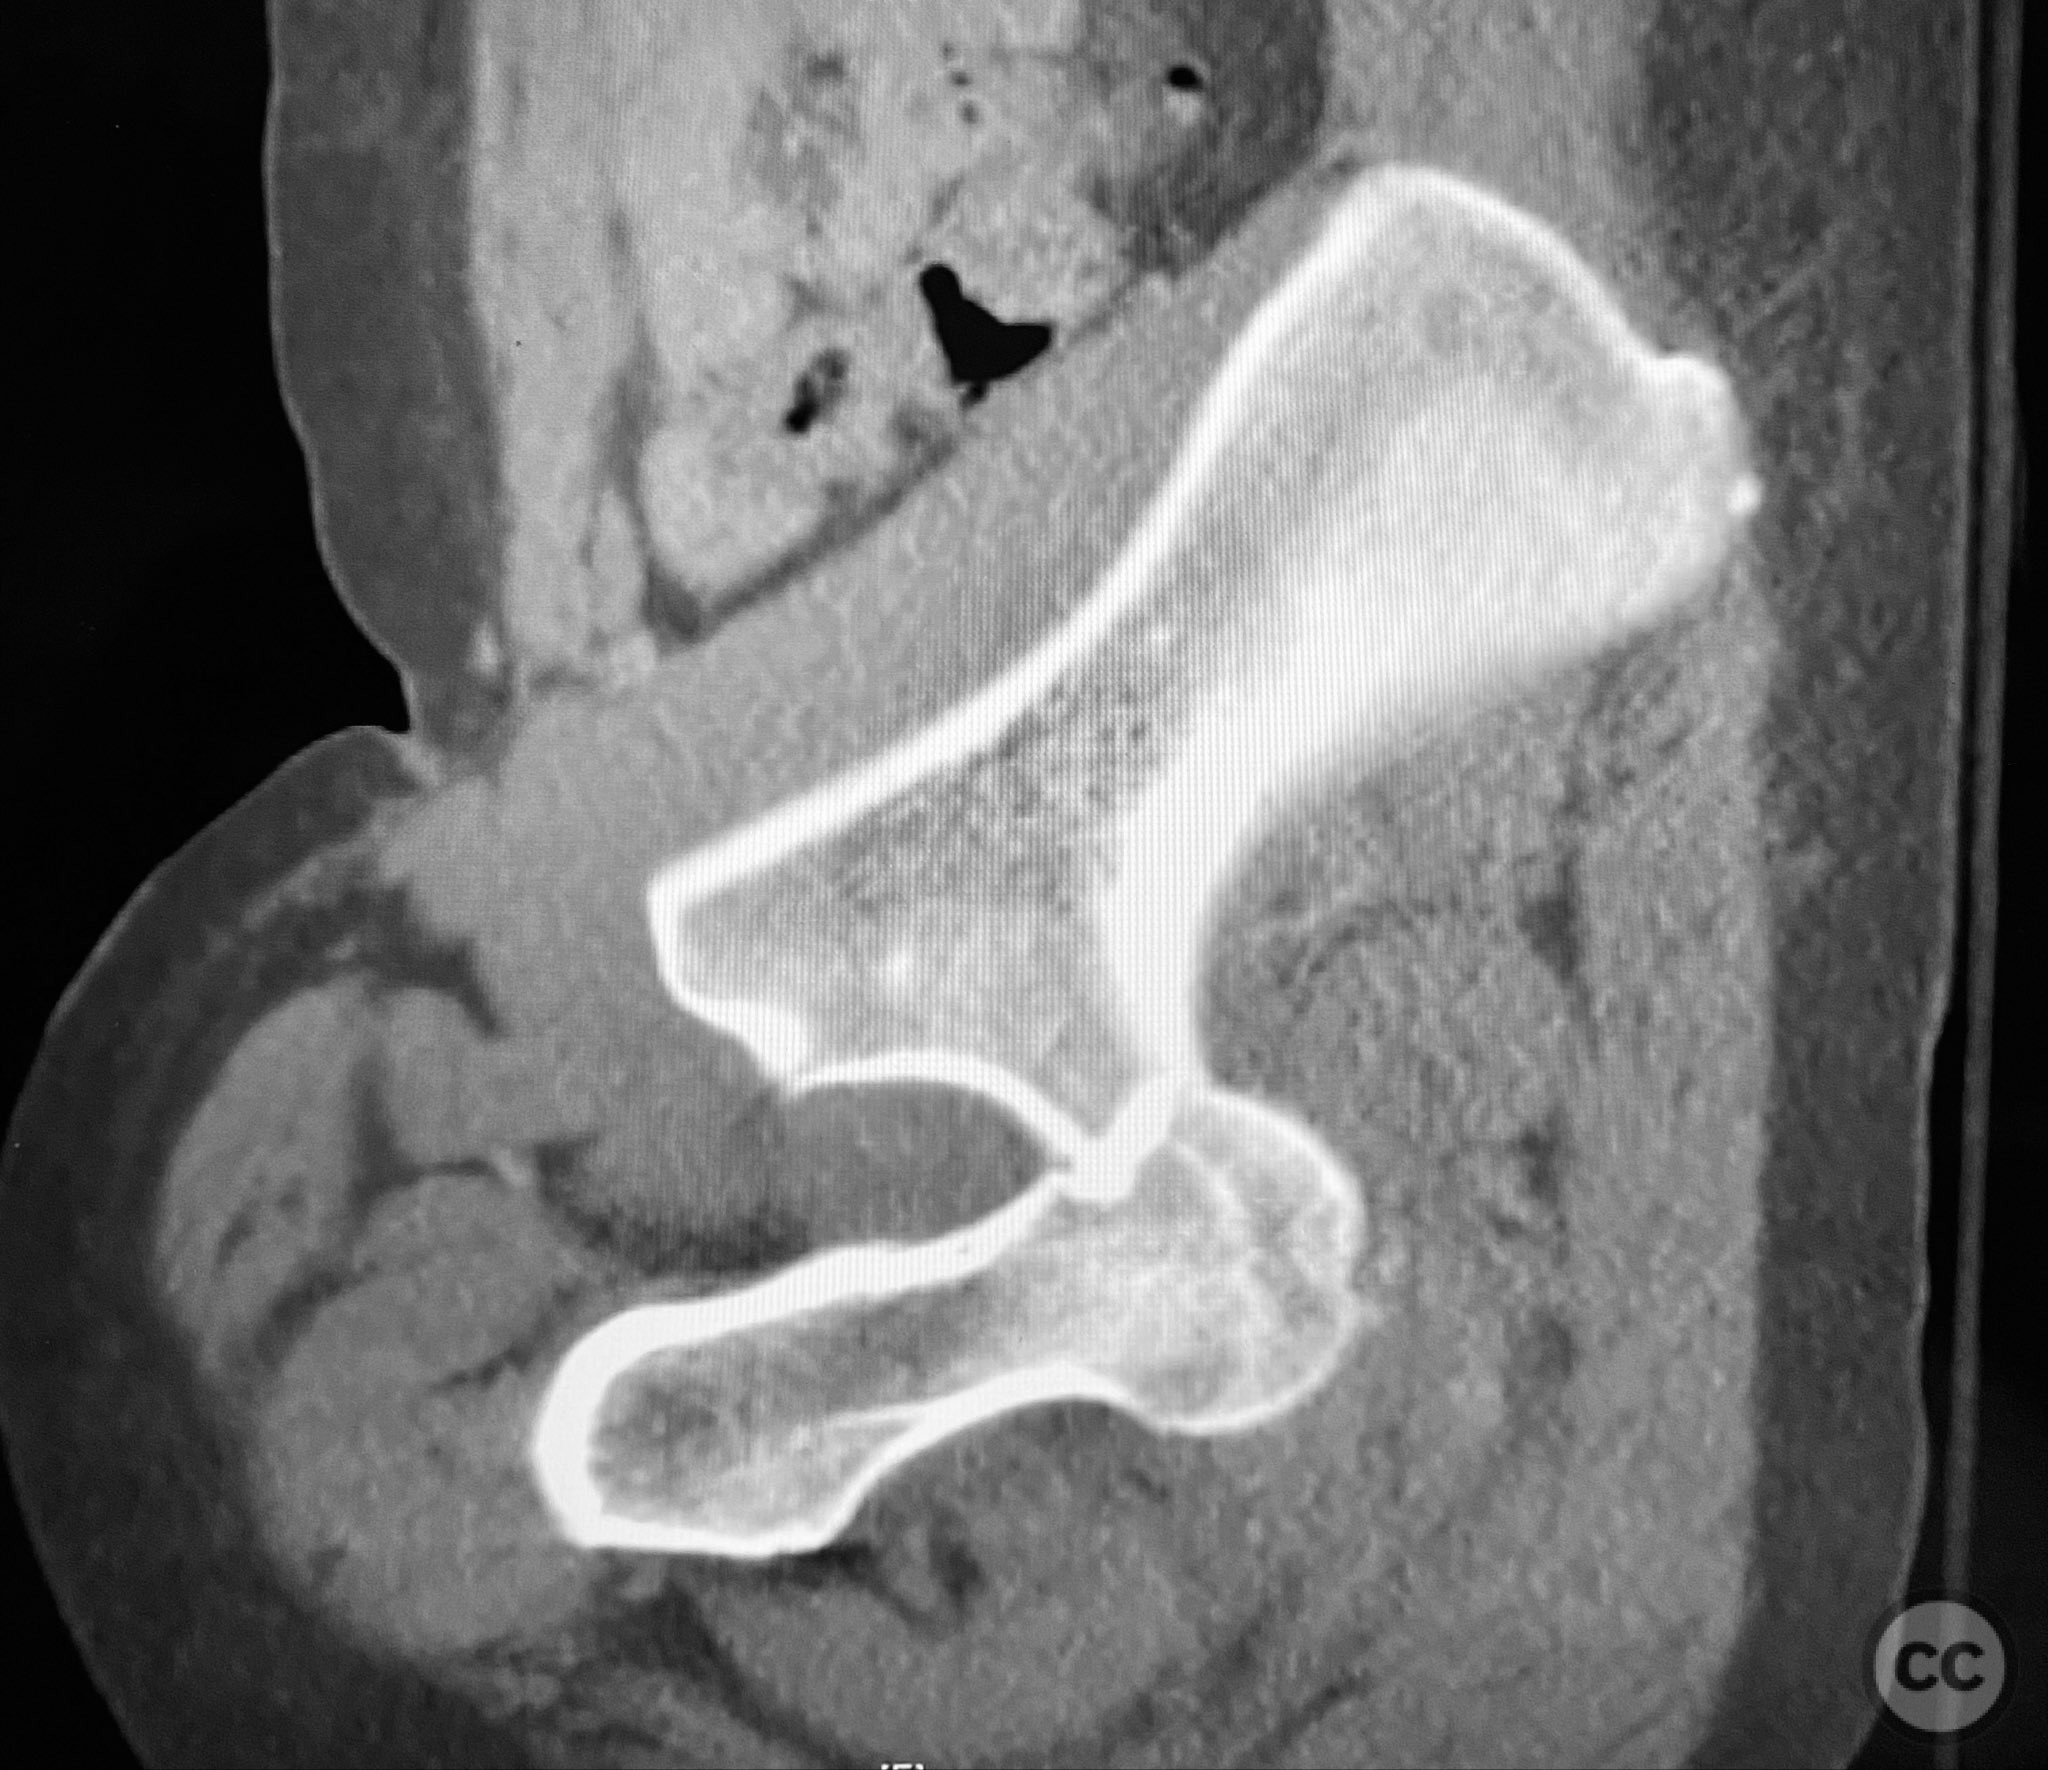

Clinical and radiological findings:  A patient sustained a posterior wall acetabular fracture-dislocation, characterized by comminution of the posterior wall, impaction of fragments into the posterior column region, and intra-articular loose fragments within the fossa acetabuli. Sagittal imaging demonstrated femoral head impalement on the intact wall, raising concern for potential irreducibility. Coronal and axial CT images revealed acetabular and femoral head impactions, peripheral wall comminution, incomplete fracture extension at the acetabular notch and quadrilateral surface, and an articular fragment within the joint. Surface renderings confirmed the extent of peripheral wall comminution and impaction. Despite these findings, a closed manipulative reduction was successfully achieved, resulting in a congruent reduction on post-reduction imaging.